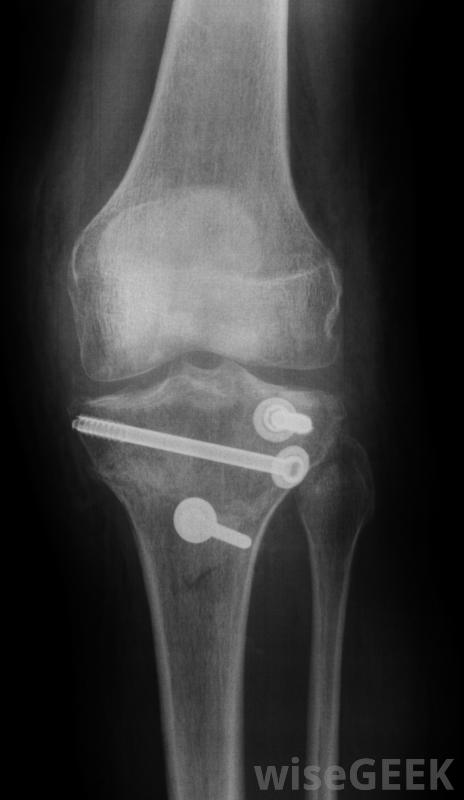

骨科手術設備可能包括塑料剪和外科鑿子。骨夾和骨科銼刀是骨科手術中使用的另外兩種設備。其他類型的骨科手術設備是骨銼和骨規。釘植入物用于固定骨段。

在骨科手術中,許多手術都需要植入金屬棒和金屬針。在這種手術中,外科醫生需要測量針、螺絲釘、螺絲釘的精確長度,一種用于切割這些金屬針的金屬絲的矯形外科手術設備是一種外科針刀。這些切割機由不銹鋼制成,擁有非常強大的下顎。

擰緊將桿和銷固定在骨頭上的螺釘。這些螺釘也可用于在手術過程中取下螺釘。這些手術鉗的手柄設計成防滑的,在外科醫生的手上很舒服。